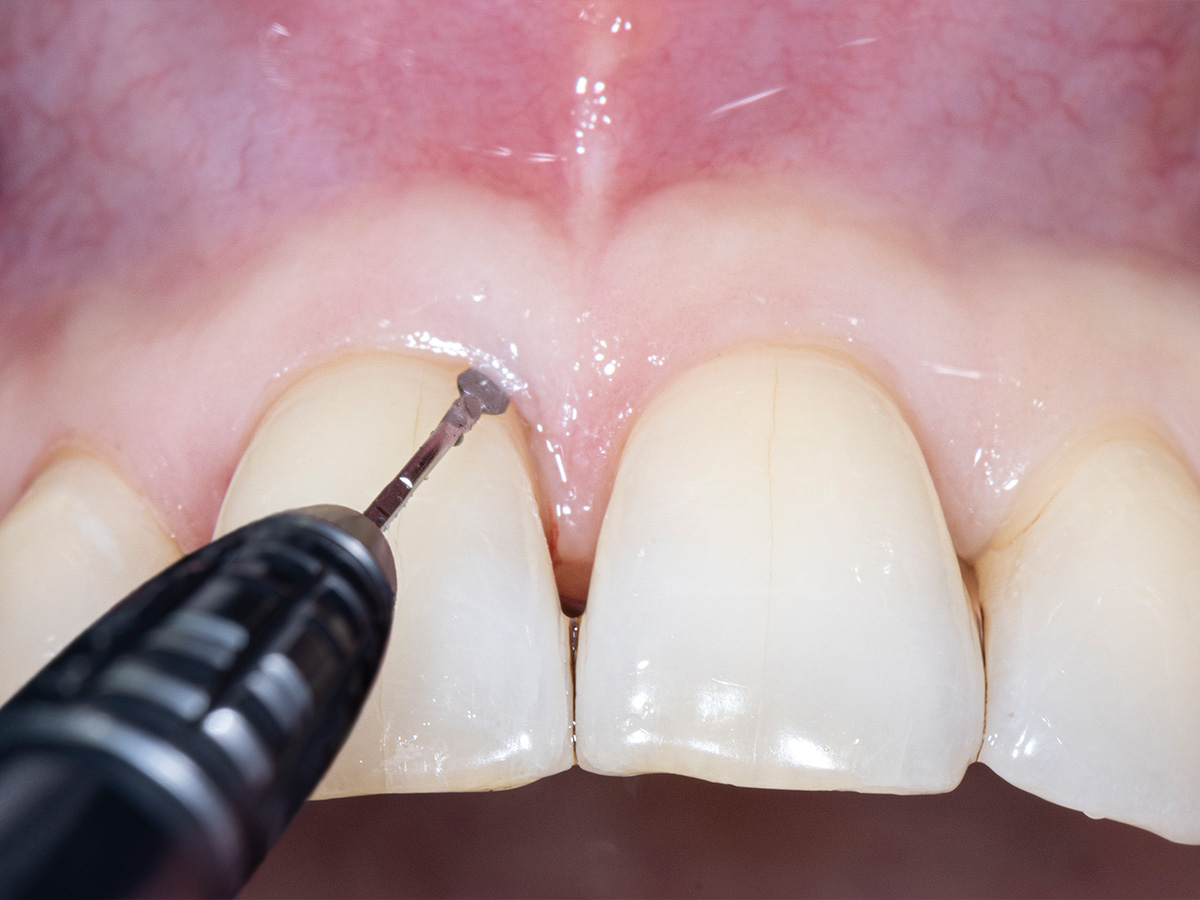

Während der intraoralen Untersuchung wurden eine erhöhte Beweglichkeit sowie erhöhte Taschensondierungstiefen und klinische Entzündungszeichen an Zahn 11 festgestellt. Ein intraorales Röntgenbild wurde angefertigt. Die intraossäre Defektkomponente gemeinsam mit dem hohen Niveau an Mundhygiene bieten eine gute Grundlage für einen regenerativ-parodontalchirurgischen Eingriff. Zehn Tage vor dem Eingriff wurde der Zahn mit dem Nachbarzahn verblockt und ein lokales Antibiotikum in die parodontale Tasche appliziert, um zum Zeitpunkt des Eingriffs möglichst entzündungsarme Verhältnisse vorzufinden. Unmittelbar vor Beginn des chirurgischen Eingriffs wurde der Defektboden mit einer Parodontalsonde ausgelotet, um Informationen über die dreidimensionale Defektmorphologie zu erhalten (Abb. 1-3).

Aufgrund der hohen Lachlinie haben wir uns für eine horizontale Inzision durch die Papillenbasis auf der palatinalen Seite sowie intrasulkuläre Inzisionen um die Nachbarzähne entschieden. Auf diese Weise können Oberflächeninzisionen auf der bukkalen Seite, die zu sichtbarem Narbengewebe führen können, vermieden werden.

Um den mesiobukkalen Aspekt des Defekts zu erreichen, wurde ein zweiter Lappen mit einer ultradünnen und biegbaren Keydent Spin Blade 360 präpariert, die an die jeweilige anatomische Situation angepasst werden kann und präzise intrasulkuläre Inzisionen im Interproximalraum sowie ein vorsichtiges Abtrennen des entzündlichen Infiltrats vom Weichgewebe und ein anschließendes sanftes Herauslösen auf die bukkale Seite ermöglicht.